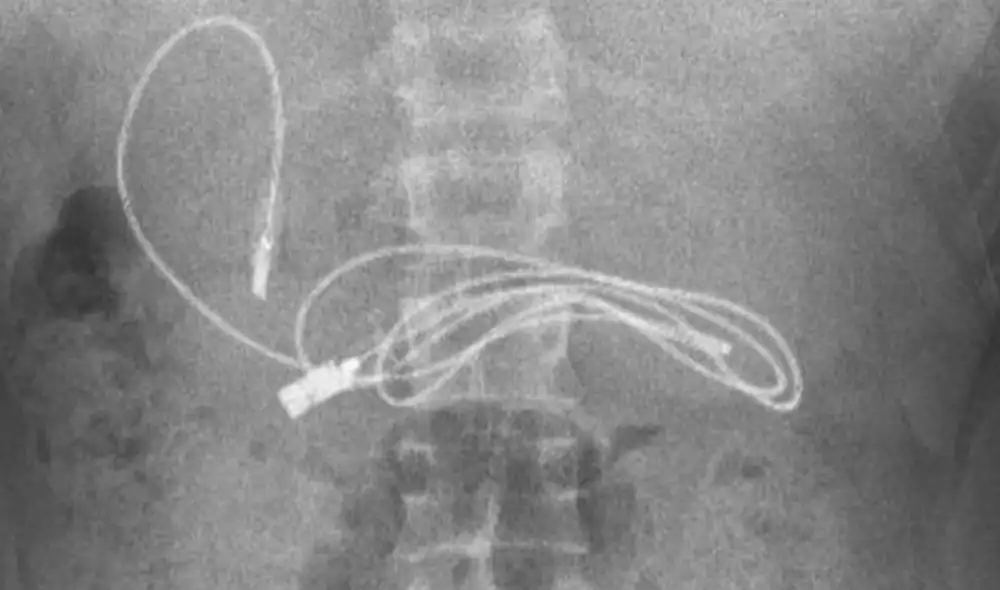

Un adolescente de 15 años tuvo que ser trasladado a un hospital de Diyarbakir, en el sureste de Turquía, luego de que presentara un fuerte malestar estomacal. Dentro de su organismo, encontraron un cable USB y una liga para el cabello.

El gastroenterólogo Yasar Dogan fue el encargado de realizar la cirugía y compartió a través de sus redes sociales las impresionantes imágenes que dan cuenta de la situación vivida por el adolescente.

Según contó, el profesional de la salud tomó la decisión de realizar una endoscopía, a través de la boca y el conducto gástrico, hasta llegar donde se encontraba alojado el cargador de celular.

“Obviamente, tuvimos dificultades para quitar el cable, ya que un extremo había pasado al intestino delgado (...) Después de que el procedimiento concluyó con éxito, el paciente fue enviado a casa con buena salud”, indicó el doctor Yasar Dogan a través de sus redes sociales.